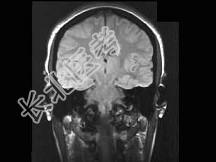

- 单项选择题男,32岁, 头痛、抽搐3年余,MRI检查如图, 最可能的诊断是 ( )

A、先天发育不全

B、灰质异位

C、正常颅脑

D、片状脑梗死

E、脑水肿